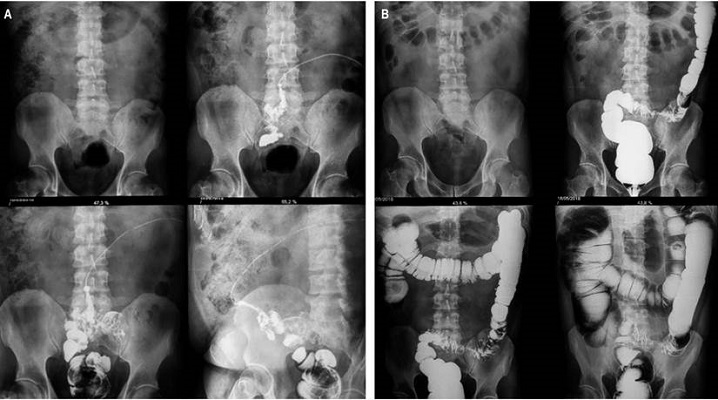

En el examen físico se constató a nivel umbilical la secreción antes descrita. El abdomen se encontraba doloroso a la palpación profunda a nivel del mesogastrio e hipogastrio sin reacción peritoneal. El resto del examen físico fue negativo. Se le realizaron los estudios necesarios para confirmar el diagnóstico de FEC, determinar las condiciones en que se encontraba el paciente y valorar la necesidad de cirugía. En la fistulografía (Figura 1A) se comprobó el conducto fistuloso y su comunicación con el colon sigmoide. El colon por enema baritado a doble contraste (Figura 1B) evidenció un estrechamiento fusiforme de todo el colon sigmoide con la presencia de divertículos. En la colonoscopía realizada se apreciaron los divertículos sin hallar masa tumoral. La biometría hemática mostró leucocitosis 10,4 × 109/L a predominio de neutrófilos (72,42 %, rango normal: 36-66).

El diagnóstico de las FEC se debe sospechar al observar la salida de contenido intestinal a través de la piel, aunque el diagnóstico definitivo se realizará al comprobar una conexión anormal entre el tubo digestivo y la piel. Con la tomografía axial computarizada (TAC) se pueden mostrar las características de la anatomía de la fístula, detectar colecciones asociadas y áreas de obstrucción intestinal distales a la fístula, identificar la enfermedad subyacente, entre otros3,6. Un estudio muy importante que generalmente ayuda a definir de manera certera la FEC es la fistulografía utilizando contraste hidrosoluble, como en nuestro paciente, en el que se pudo evidenciar la conexión del ombligo con el colon sigmoide (Figura 1). También puede ser útil un estudio gastrointestinal con contraste (tránsito intestinal o enema baritado de colon en función de la sospecha del tramo intestinal afectado)1.